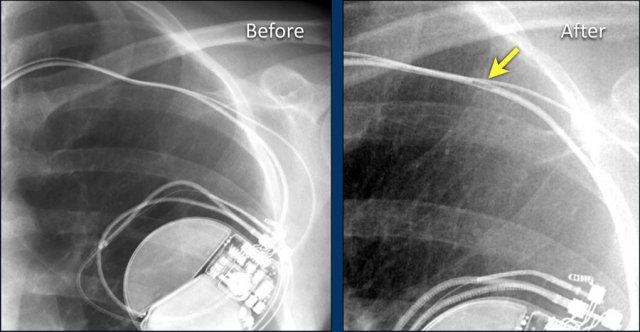

Hình ảnh được chụp ngay sau khi đặt ICD.

Có hình ảnh tràn khí màng phổi nhỏ (mũi tên).

Đây là biến chứng thường gặp nhất.